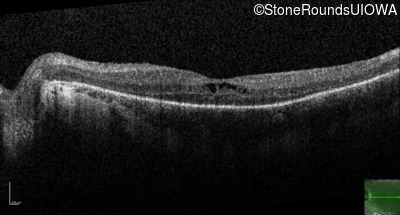

Optical Coherence Tomography - Left - 20/50

Exemplar / OCT Stack